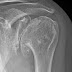

We had the opportunity to care for a 60 year old patient with a painful dysplastic shoulder. At the time of presentation the patient could perform only 3 of the 12 functions of the Simple Shoulder Test. The preoperative films are shown here

While some surgeons may have considered a total shoulder with a posteriorly augmented glenoid component, a posterior bone graft or a reverse total shoulder, we offered her a hemiarthoplasty with soft tissue balancing. No CT scans were needed to plan this surgery. No attempt was made to change glenoid version.